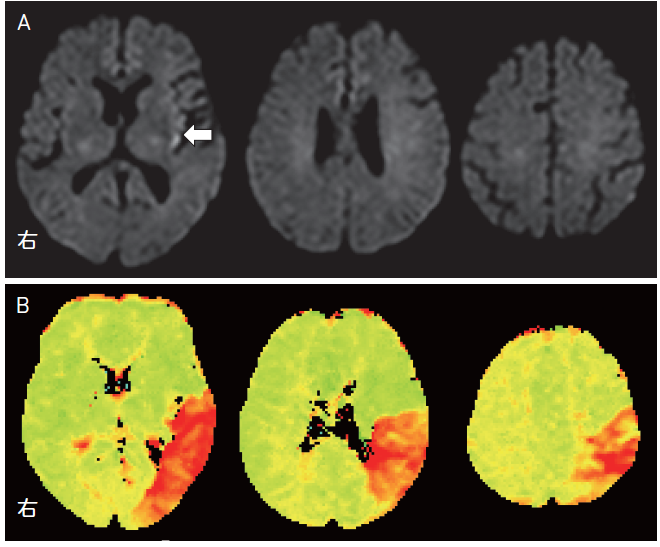

A:そうです。入院時の頭部MRI がこちらです(図5-1)。拡散強調画像(図5-1A)で左の島皮質に高信号を認めました。脳灌流画像(図5-1B)では,縁上回・角回を含む左頭頂葉から側頭葉後部にかけて灌流障害を認めていました。

K:脳梗塞の領域は灌流障害の領域よりもかなり小さかったんだね。